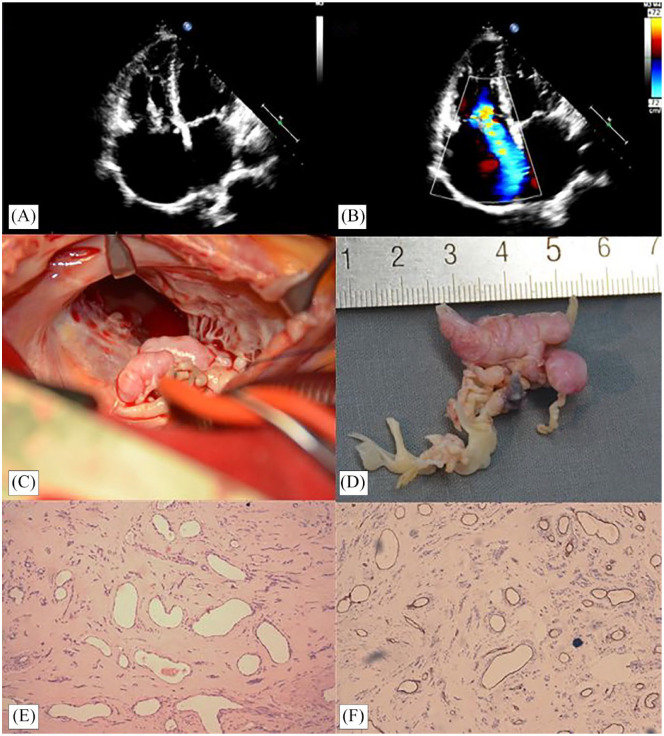

Introduction: Cardiac hemangioma is one of the rarest tumors, with only a few cases described. Unlike other cardiac tumors, its symptoms are nonspecific, making misdiagnosis easy. Cardiac hemangioma can present with various clinical manifestations, including valve disorder, arrhythmia, pericardial effusion, and embolism. Echocardiography is the most direct examination, and surgical resection the simplest and most effective treatment.

Patients and methods: We present a new case of lobulated cardiac hemangioma causing tricuspid regurgitation and discuss the clinical features, diagnosis, and treatment of this rare tumor.

Results: After surgical resection and tricuspid valve replacement, the patient recovered well.

Conclusion: For cardiac hemangiomas involving the tricuspid valve, tumor resection combined with valve surgery is an effective treatment option.